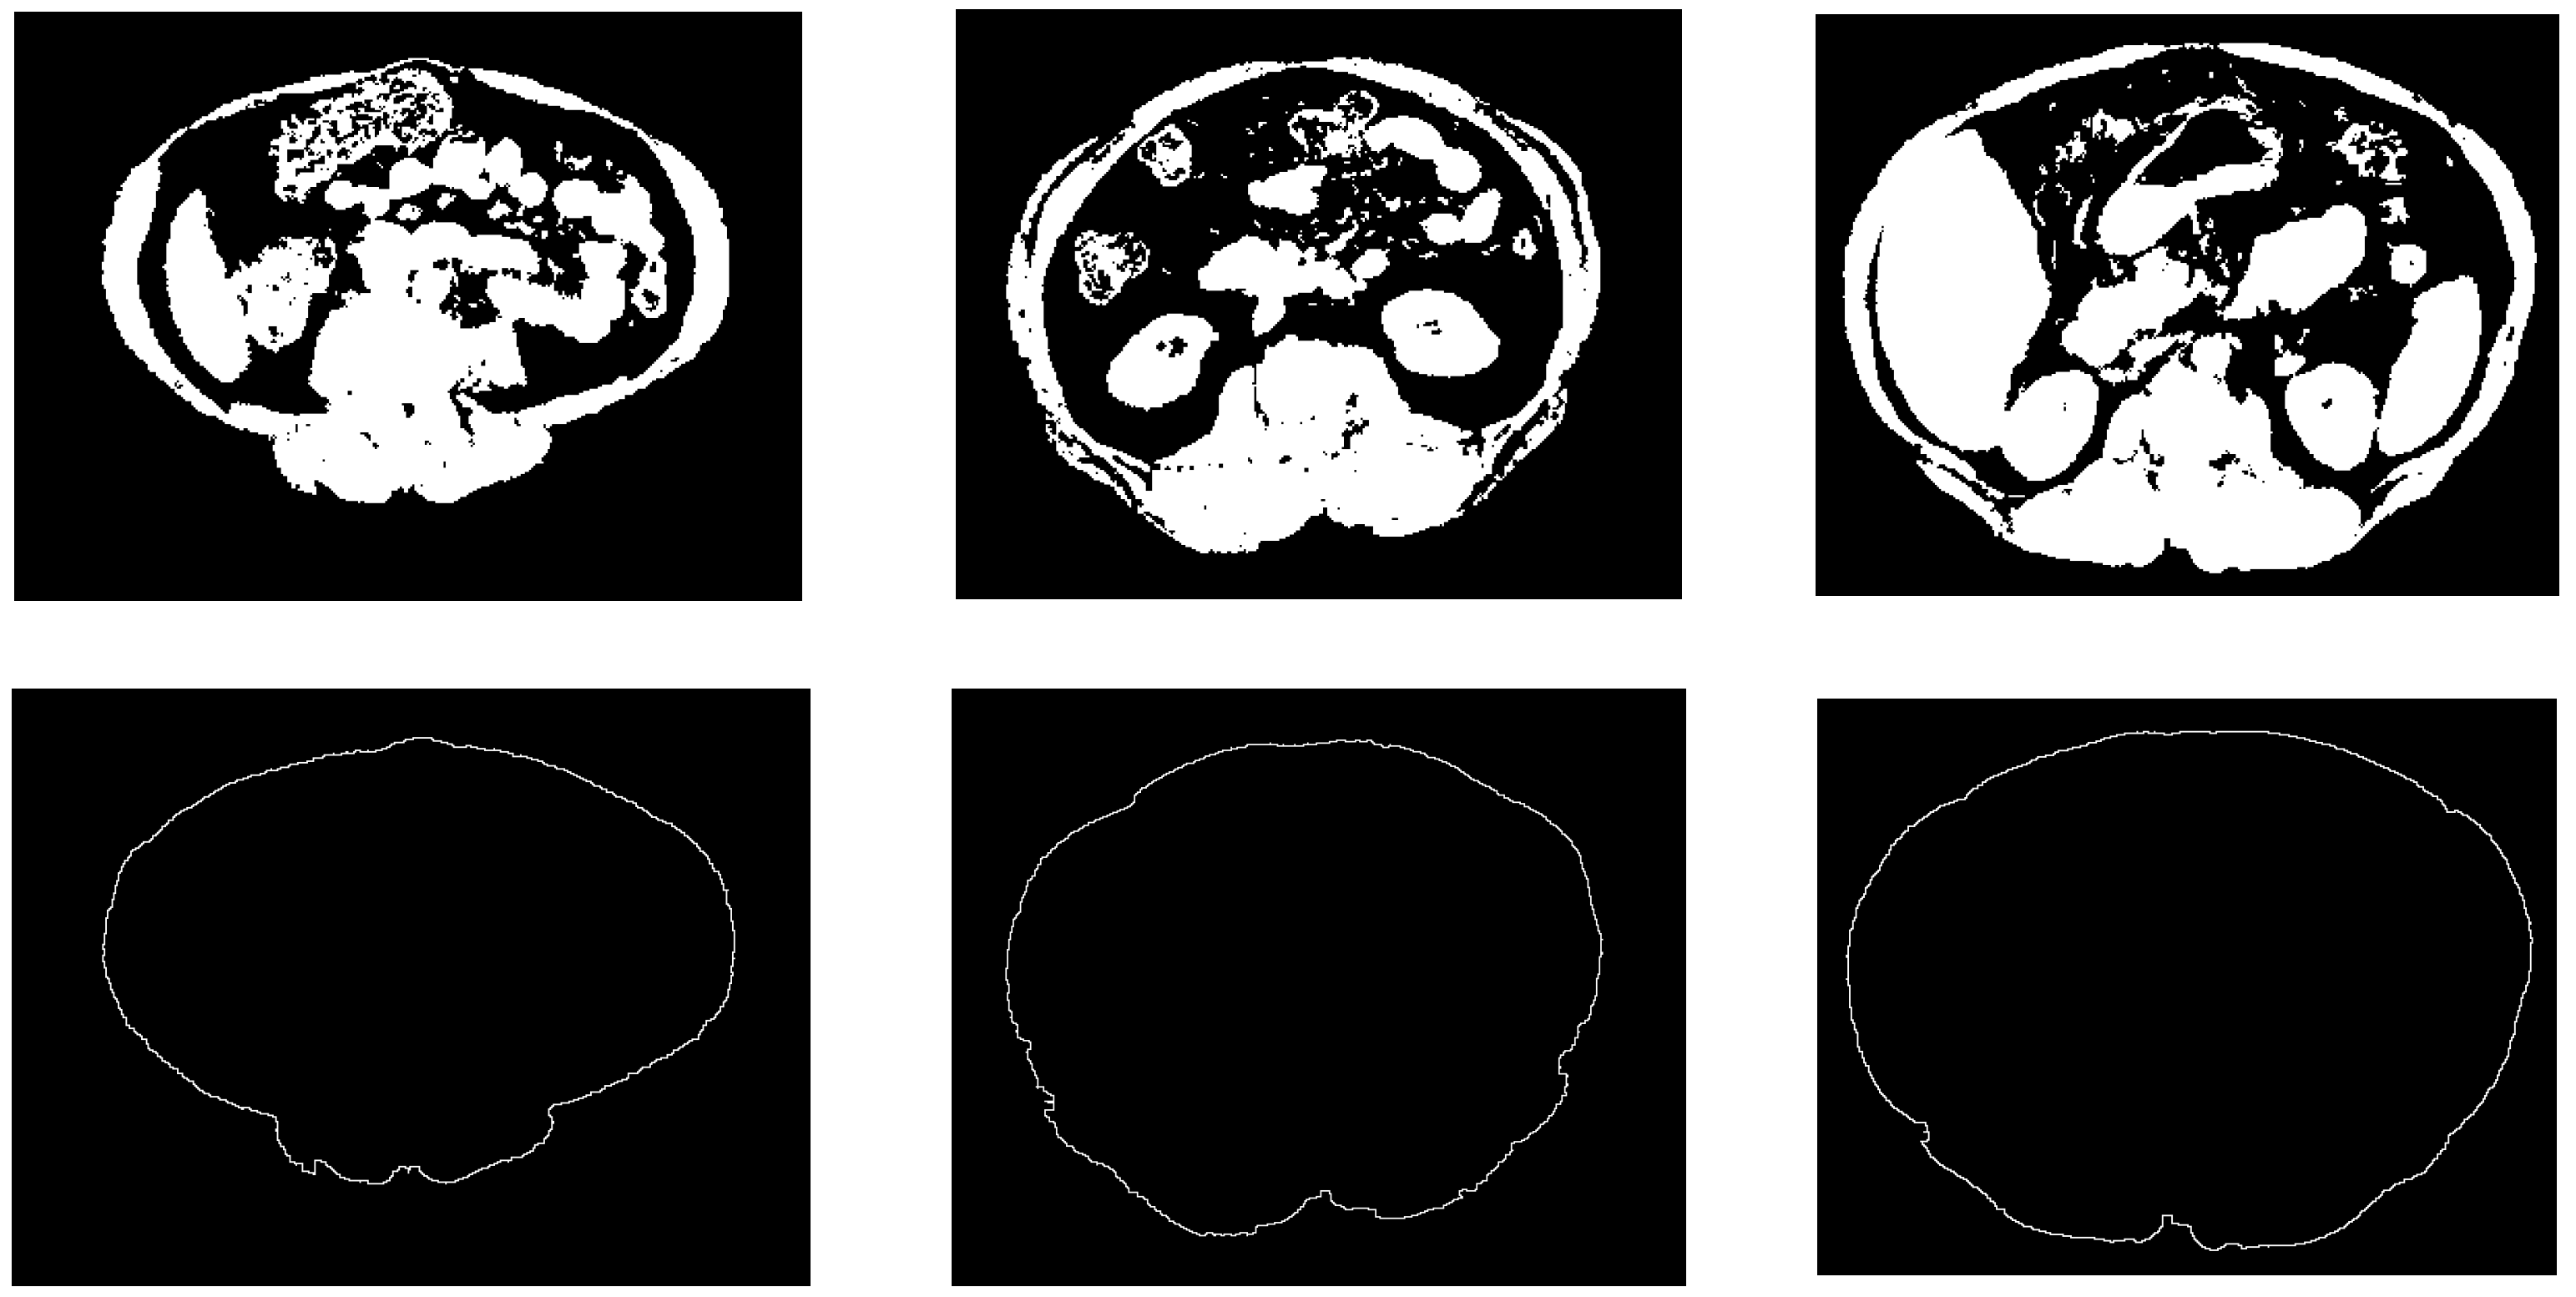

Figure 7 shows some examples of the obtained results of the constructed abdominal wall using the proposed method.

Figure 7.

Samples from the abdomen wall boundary detection results. The top row is the non-fat binary images, the bottom row is the abdomen wall boundary images.

The classification of abdominal fat tissues deserves special attention. In the proposed method, we studied all the issues relating to the classification operation and considered them during the design stages. Figure 8 shows the structure of the proposed abdomen fat segmentation method.

The fat classification method started by segmenting the SF from the fat binary image by applying element-wise logic and operation between the fat binary image and the inverse of the filled abdomen wall boundary image. Subtracting the SF binary image from the fat binary image produced a binary image where foreground pixels represented the VF. Figure 9 shows the steps of the classification process illustrated by an example.

Figure 9.

SF and VF classification operation.